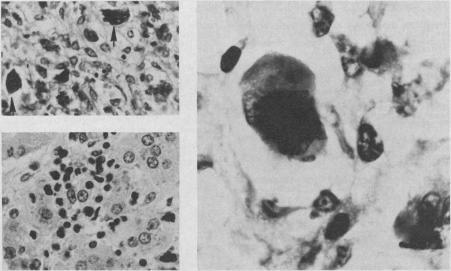

A 58-year-old woman presented with pericarditis and pericardial effusion. Investigation revealed that she was suffering from a thrombocythemic myeloproliferative disorder; she died of massive pulmonary embolism 10 days after admission. Histologic study verified epicardial and pericardial trilineage hematopoiesis. Pericarditis is an unusual feature of essential thrombocythemia and it may occur in direct relation to the abnormal cellular proliferation.

一名58岁女性因心包炎和心包积液就诊。检查发现她患有血小板增多性骨髓增殖性疾病;入院10天后死于大面积肺栓塞。组织学研究证实心外膜和心包存在三系造血。心包炎是原发性血小板增多症的一个不寻常特征,可能与异常细胞增殖直接相关。